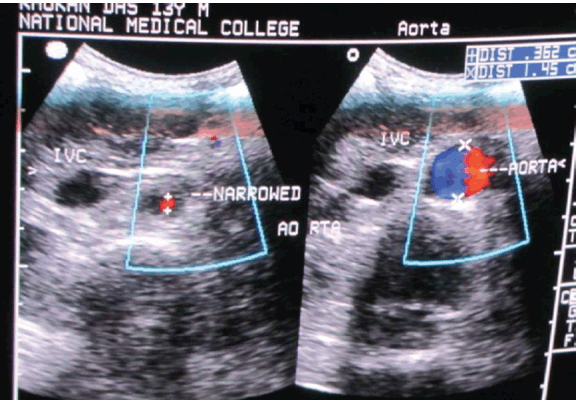

A 13-year-old boy was admitted with persistent headache and vomiting for one month and repeated generalized tonic clonic seizures for two days. He had no history of fever, chest pain, palpitations, claudication or visual disturbance. Enquiry about joint pain, photosensitivity, oral ulcers and recurrent infections were not contributory. His past history was unremarkable and his parents had no reason to worry about his milestones. The boy had good scholastic performance and had no difficulty in outdoor games. There was no history of contact with tuberculosis. Clinical assessment revealed an alert, conscious and co-operative boy, with corroborative apparent and chronological ages. Clinical examination of the patient showed blood pressure was 240/150 mmHg in both the upper limbs, and all peripheral pulses were palpable. Blood pressure was similar in upper and lower limbs and no radio radial or radio femoral delay was appreciated. Edema was absent and neck veins were not engorged. Systemic examination was unrewarding except for a systolic bruit heard over the epigastrium, which extended along the midline up to 1 cm above the umbilicus. Ophthalmoscopy was normal as well. Counts, baseline biochemistry (sugar, urea, creatinine, LFT, lipid profile, Na, K, TSH and FT4) and ECG were all within normal limits. X-ray of chest suggested borderline left ventricular hypertrophy and echocardiography with Doppler demonstrated eccentric hypertrophy of the left ventricle (left ventricular internal diameter 4.35 cm, LVIDs 2.98 cm, LVEF 60%). Moreover, a localized narrowing of a suprarenal segment of the abdominal aorta with a systolic pressure gradient around 40 mmHg, systolic pressure gradient 100 mmHg in celiac axis and superior mesenteric arteries. (Figure 1) Ultrasonography (USG) of abdomen with Color Doppler was done. Kidney sizes were 10.6 cm (right) and 8.5 cm (left) in the long axes. The right renal artery and interlobar arteries demonstrated normal spectral waveforms but the left renal artery could not be imaged properly. An abrupt focal dilatation of the abdominal aorta 1.7 cm (approx.) below the origin of superior mesenteric artery was observed. The dilated segment spanned 6.27 cm in the craniocaudal direction and measured 1.6 cm in diameter. A focal narrowing just before the dilatation was noted on USG. (Figure 2) In view of the seizures prior to admission, contrast enhanced computed tomography (CT) of brain was performed and bilateral symmetrical non-enhancing hypodense lesions involving the parieto-occipital areas suggestive of infarcts were noted. But repeat CT scan was normal and suggesting the diagnosis of reversible posterior leukoencephalopathy rather than infarct. Contrast enhanced computed tomography (CECT) abdomen corroborated the findings on USG and showed relatively small left kidney with poor enhancement patterns, suggestive of left renal artery stenosis. A focal dilatation of the abdominal aorta was also noticed on the CT scan. Tests for ANF (HEp2 method), RA factor and cANCA were all unrewarding. Magnetic resonance angiography of the aorta and its branches were performed. This showed a normally located aortic arch and the ascending aorta was seen to arise from the left ventricle with no evidence of any abnormal dilatation or flap. The arch of aorta and thoracic aorta were also normal. A distinct fusiform dilatation of abdominal aorta was seen just below the origin of the superior mesenteric artery. This dilated segment had a diameter of 19 mm and the craniocaudal extension of the dilated segment was about 63 mm. Focal narrowing of abdominal aorta as well as left renal artery was noted just proximal to the dilatation. The dilated segment extended below up to the division of aorta into the iliac vessels. (Figure 3) The boy was referred for vascular surgery but the patient refused any operative procedure. He was put on metoprolol (50 mg) twice daily and amlodipine (10 mg) daily and has been on irregular follow-up for the last 14 months, his last blood pressure record was 160/90 mmHg.

Cursor on image to zoom/Click text to open image

Figure 1: Echo Doppler study showing narrowed aortic segment with pre-stenotic dilatation.